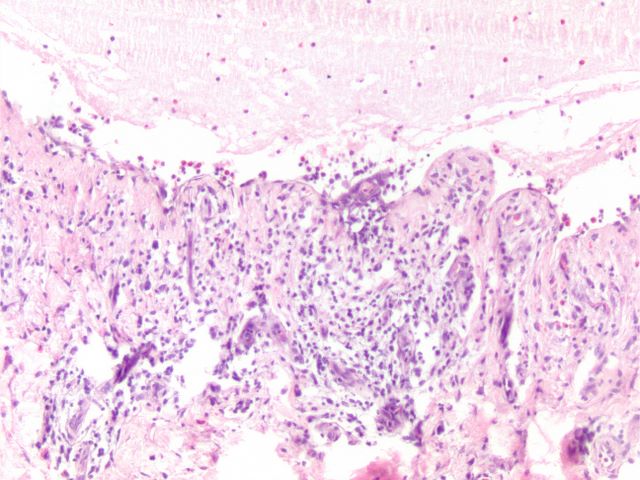

538 -- image4.jpg